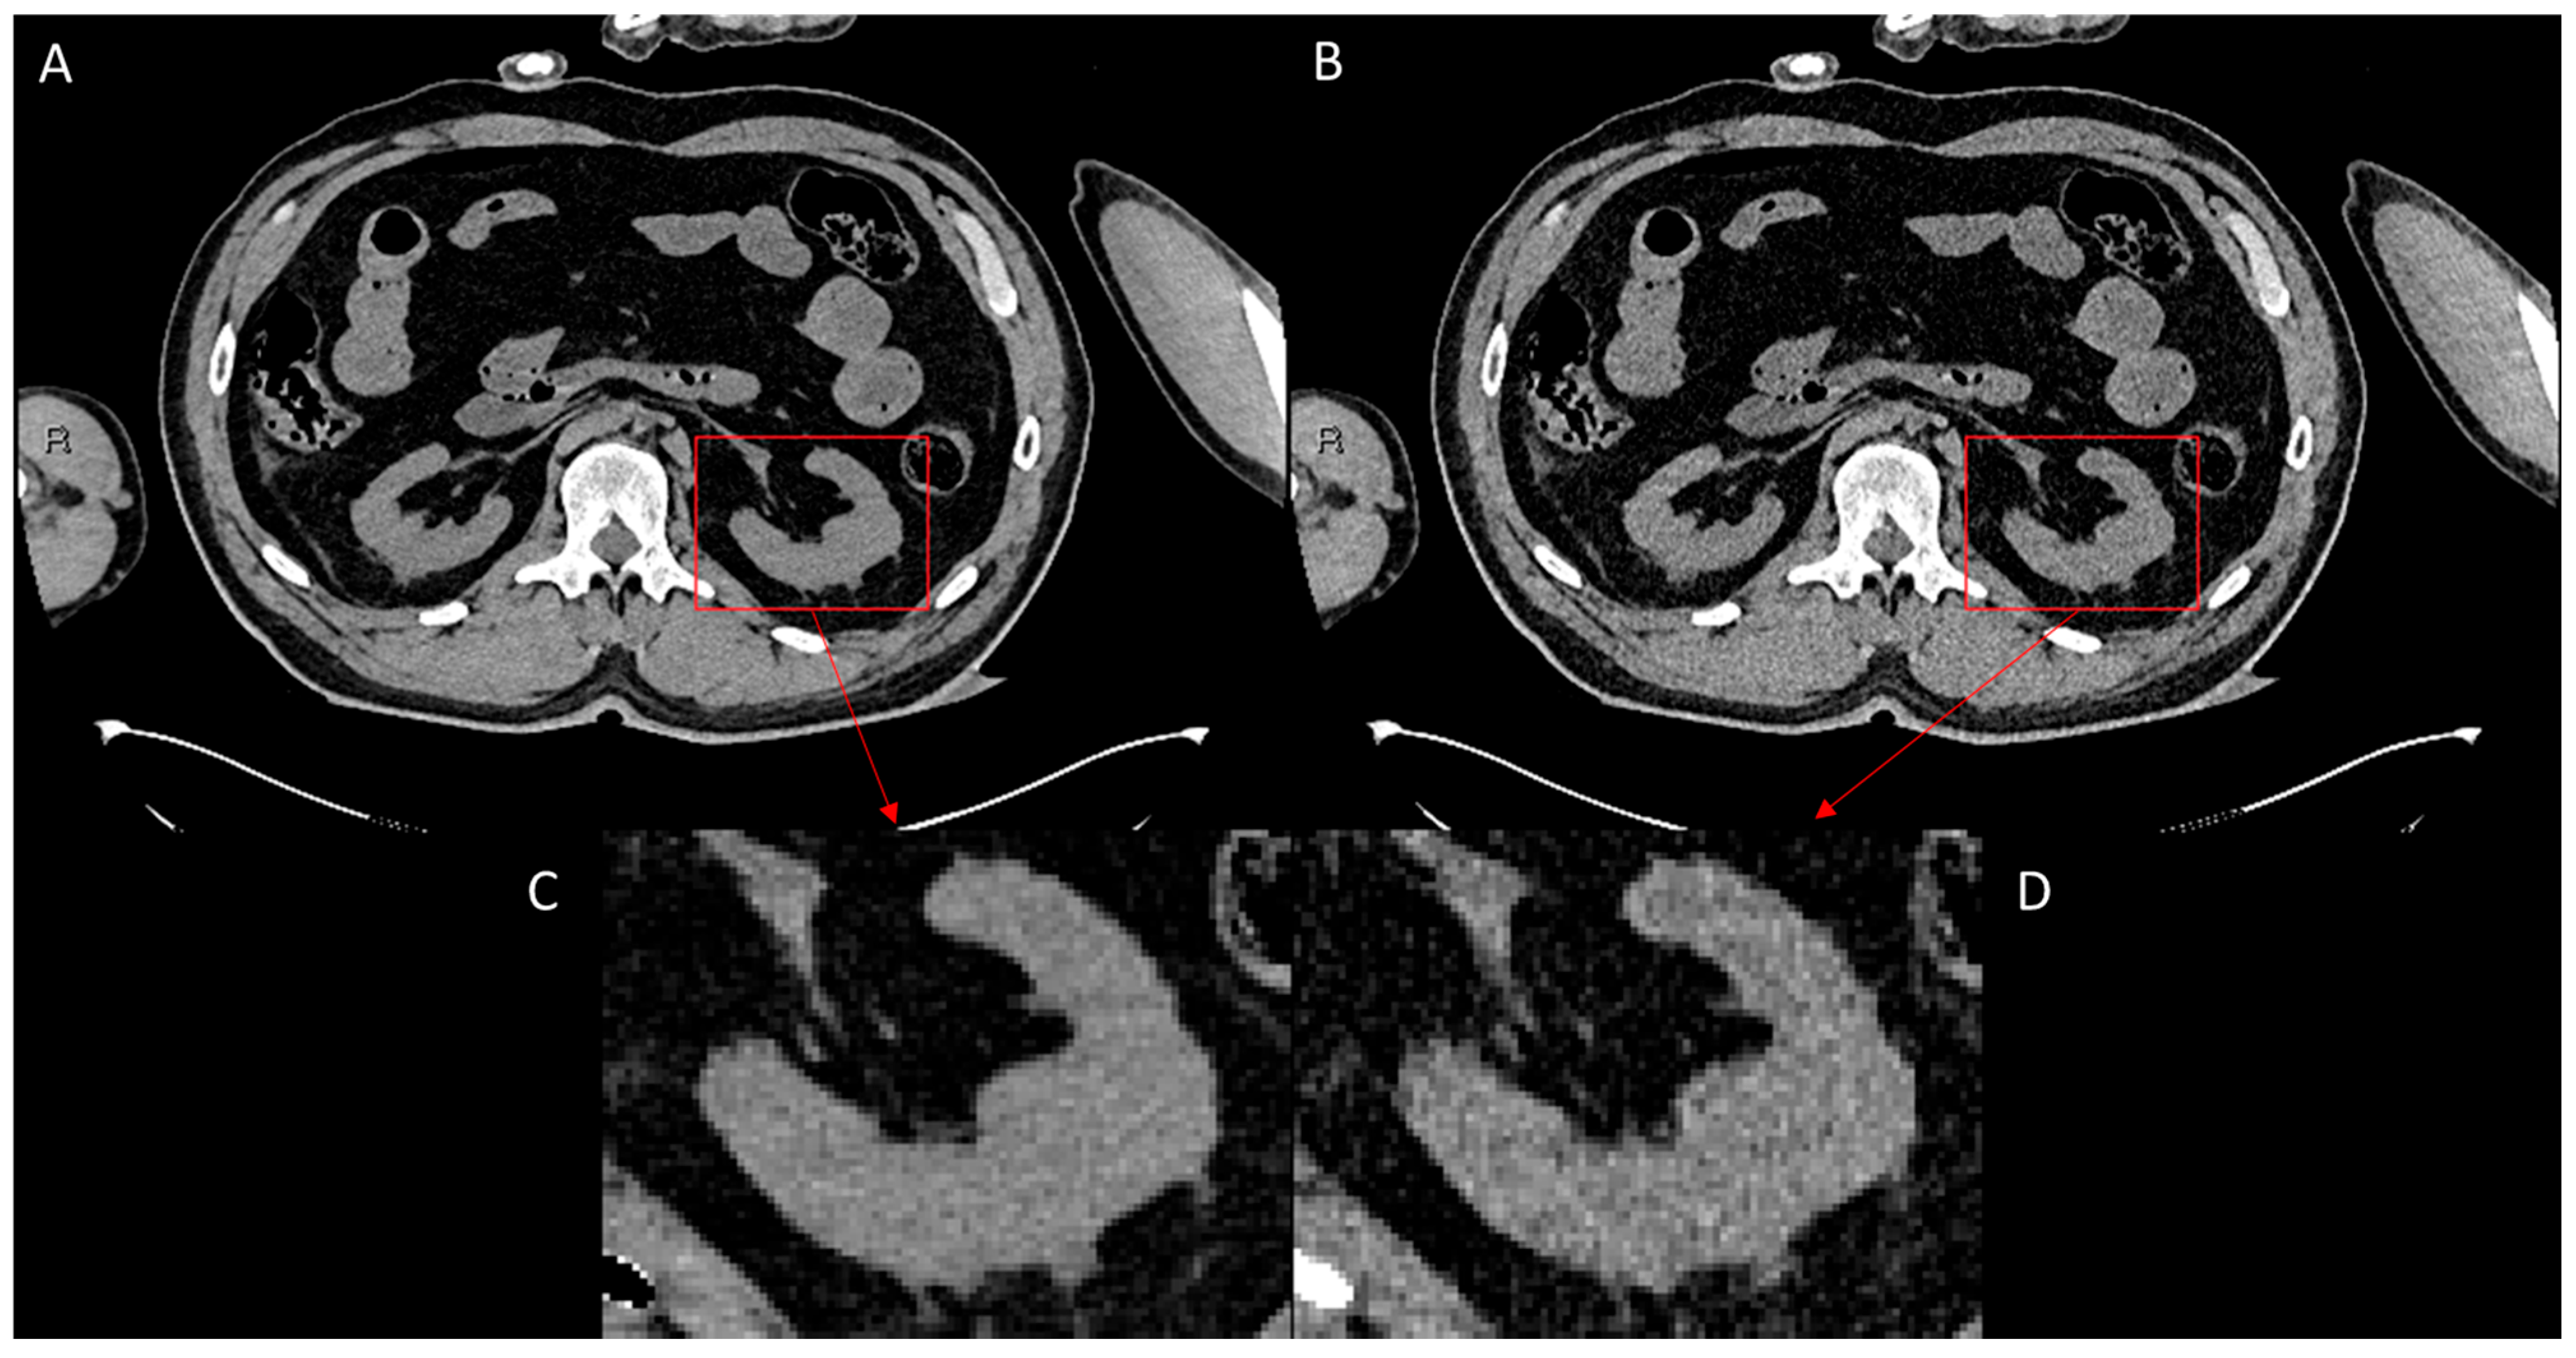

- Increased PSNR from an average of 30.78 in the LQ images to 31.32 in the ErisNet-processed images, with a SD of 3.69;

- Substantially reduced MSE from 73.45 in the LQ images to 64.70 in the ErisNet-processed images;

- Increased the SSIM values from 0.92 to 0.94;

- Increased VIF from 0.47 in LQ images to 0.49;

- Did not compromise EPI, which was 0.97 in LQ images and 0.97 with ErisNet;

- Decreased noise variance from 73.43 in LQ images to 64.69 in ErisNet;